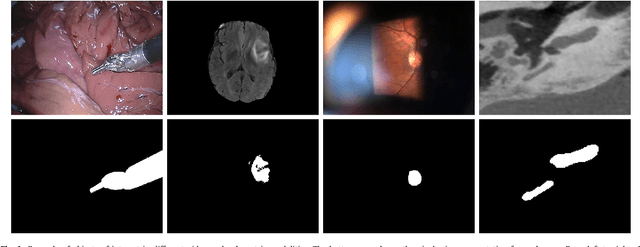

Recent machine learning strategies for segmentation tasks have shown great ability when trained on large pixel-wise annotated image datasets. It remains a major challenge however to aggregate such datasets, as the time and monetary cost associated with collecting extensive annotations is extremely high. This is particularly the case for generating precise pixel-wise annotations in video and volumetric image data. To this end, this work presents a novel framework to produce pixel-wise segmentations using minimal supervision. Our method relies on 2D point supervision, whereby a single 2D location within an object of interest is provided on each image of the data. Our method then estimates the object appearance in a semi-supervised fashion by learning object-image-specific features and by using these in a semi-supervised learning framework. Our object model is then used in a graph-based optimization problem that takes into account all provided locations and the image data in order to infer the complete pixel-wise segmentation. In practice, we solve this optimally as a tracking problem using a K-shortest path approach. Both the object model and segmentation are then refined iteratively to further improve the final segmentation. We show that by collecting 2D locations using a gaze tracker, our approach can provide state-of-the-art segmentations on a range of objects and image modalities (video and 3D volumes), and that these can then be used to train supervised machine learning classifiers.